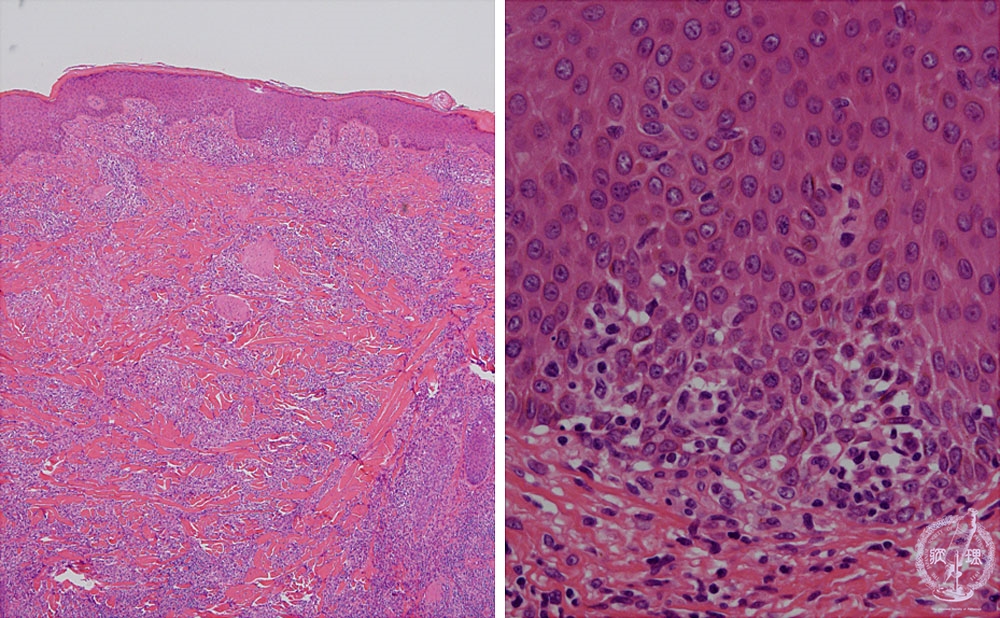

- (11)Malignant lymphoma of the skin (Mycosis fungoides)

Microscopic findings: In advanced stage (tumor stage), lymphoma cells are diffusely seen in the dermis with epidermotropism (inside the circle).